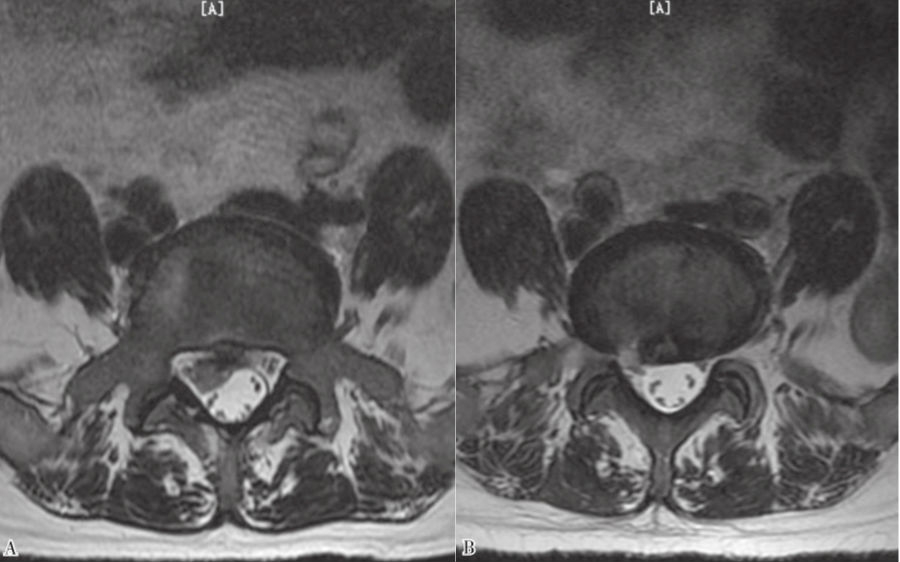

9. 术后复查MRI。(图43、图44)

图43 术前和术后MRI轴位对比

A. 术前腰椎MRI轴位;B.术后腰椎MRI轴位